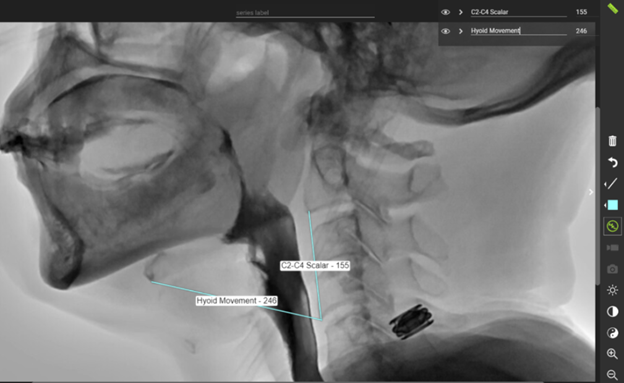

Peak Hyoid Movement Using the C2 - C4 Scalar

Quick Takeaways

This measure provides the peak hyoid excursion as a percentage of the cervical spine length.

Steps for Completion

Using frame-by-frame review, find the frame of peak hyoid movement.

Set the scalar using the line tool by drawing a line from the bottom corner of C2 to the bottom corner of C4.

Draw a line from the bottom of C4 to the bottom front corner of the hyoid when the hyoid is at its peak movement.

Divide the hyoid movement by the C2-C4 scalar x 100.

Ex. 246/155 = 1.58 x 100 = 158%

This means that the hyoid movement is 1.58 x the length of C2-C4.

Example: Use of the line tool in TIMS MVP to assess peak hyoid movement.